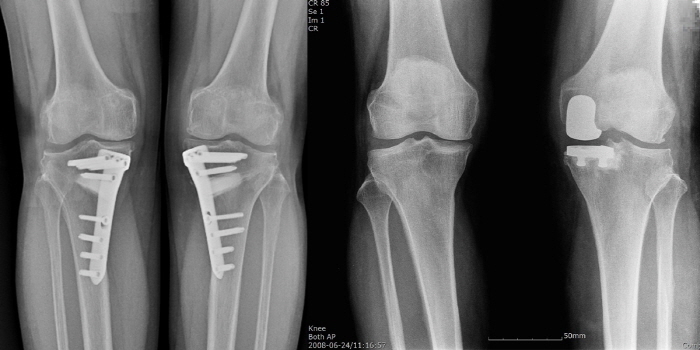

따라서 젊은 퇴행성 관절염 환자들은 전체 치환술 대신 ‘부분 인공관절 치환술’과 ‘근위경골 교정절골술’을 적용하는 것이 좋다. 부분 인공관절 치환술은 말 그대로 관절의 일부만을 인공관절로 교체하는 수술을 말한다. 일부만 교체하기 때문에 손상된 부위가 아닌 건강한 부분은 보존이 가능하다. 수술 시 절개와 출혈이 적고 일상 회복이 빠른 편이며, 수술 이후에도 관절 운동의 각도를 살릴 수 있다. 또한 비교적 활동성이 적고, 통증이 심한 환자, 빠른 수술 회복을 원하는 환자들에게 적용해볼 수 있다.

근위경골 교정절골술은 하지의 비정상적인 축을 바로잡아 무릎의 하중을 건강한 관절로 옮기는 치료법이다. 관절의 정렬과 하중의 분포를 개선해 통증을 없앨 수 있다. 부분 인공관절 치환술보다 수술 이후 관절 운동 범위나 활동성이 뛰어나기 때문에 평소 활동적이고 야외 활동을 즐기는 사람들에게 권장한다.